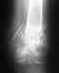

Здравствуйте. 2 апреля я сломала б/берцовую кость. 12 сделали зимо со статическим блокированием, но поставили не те спицы котые мы купили.

Поставили наши, а мы брали импортные.Обещали что пойду через месяц, но прошло уже 3 месяца, а у меня не идет сращение кости. Не могли бы вы сказать почему? еще мне во время операции задели нерв, который идет к большому пальцу, из-за этого он не работает.Я ходила на электрофорез с прозерином не помогло. Электоростимуляця не пошла-очень больно. Скажите пожалуйста возможно ли ускорить сращение и как то восстанивить нерв? спасибо

Верятно, то, что использовали другой стержень, было обусловлено тем, что во время операции купленный не подошел по размеру. Но сделано все неплохо и с этим стержнем.

Вам уже с месяц пора ходить с полной нагрузкой, т.е. без трости и костылей. Это так?

Если гвоздь был заперт статически, также уже пора его отпереть, убрав один винт вверху - это сделано?

Если сращение не наступит через 2-3 мес. после динамизации гвоздя и ходьбы с полной нагрузкой (это крайне редко, но бывает), оптимально будет заменить стержень на другой, большего диаметра. Как правило, это решает проблему.